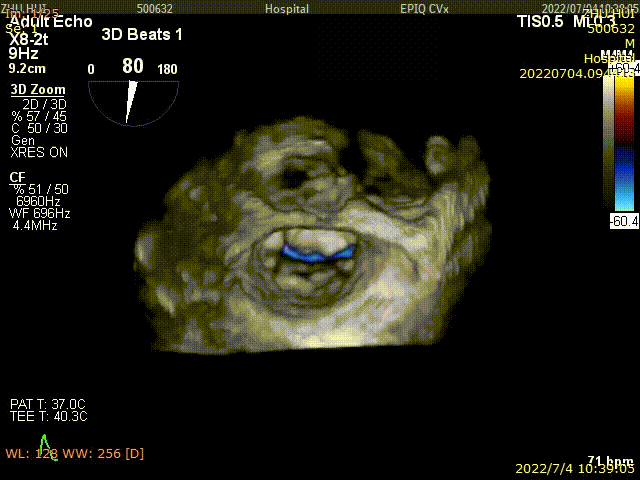

术后TEE显示,二尖瓣双孔化形成,反流明显减少